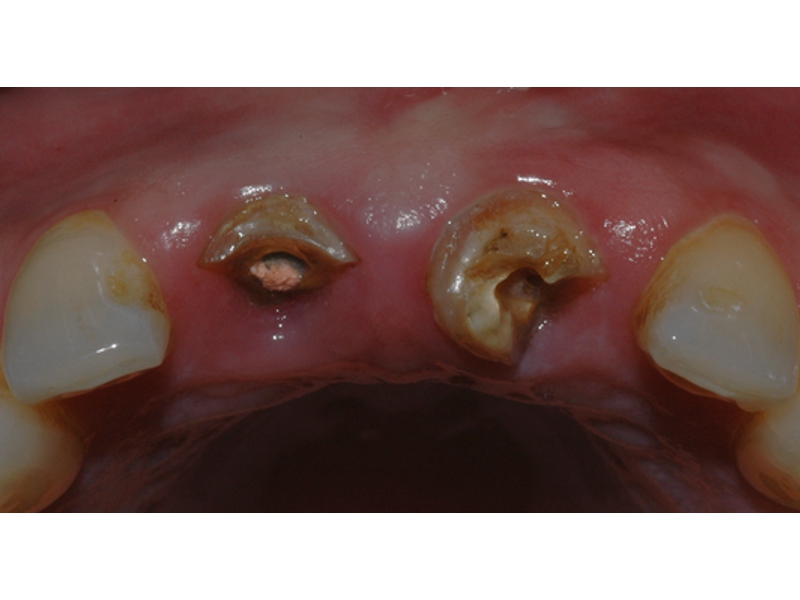

DENTÍSTICA

É o ramo da odontologia que atua na área da cosmética e restauração dental. Entre outros serviços, os profissionais desta especialidade tratam de clareamentos dos dentes, uso de resinas diretas e indiretas, facetas laminadas, inlays/onlays cerâmicos (blocos estéticos) e restaurações estéticas.

Podemos incluir nesta especialidade as lentes de contatos odontológicas ou laminados cerâmicos, que são estruturas cerâmicas ultrafinas, podendo ter apenas 0,2 mm de espessura, possibilitando assim um tratamento altamente estético e minimamente invasivo, com mínimo desgaste ou em determinadas situações nenhum desgaste dentário

As lentes de contato são normalmente indicadas por razões estéticas, sendo capazes de corrigir desde pequenas imperfeições de forma dental até dentes anteriores com pequenas fraturas ou com diastemas.

Podem ser usadas ainda para disfarçar manchas dentárias e pequenas descolorações. Tem como foco a estética, ainda que a restauração de dentes também seja uma medida importante para a saúde individual, já que a permanência de cáries pode causar problemas a vários níveis, além de criar problemas na mastigação dos alimentos